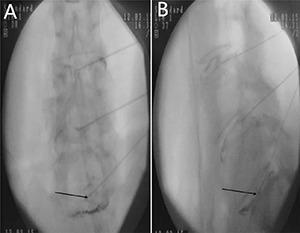

To explore value of different radiographic indexes in the diagnosis of discogenic low back pain (LBP). A total number of 120 cases (60 patients diagnosed with discogenic LBP and 60 healthy people) were retrospectively analysed to identify factors in the diagnosis of discogenic LBP by using univariate and multivariate analyses. A receiver operating characteristic (ROC) curve was drew to show the predictive accuracy of the finally enrolled factors. Among all the included patients, 60 were strictly admitted in the discogenic LBP group while the other 60 were enrolled in the control group. Five results shows significant differences between discogenic LBP and control groups, including Cobb angle, lumbar stability, height of the disc, Modic change and High intense zone (HIZ) based on the results of univariate analysis; lumbar stability, Modic change and HIZ show high value in the diagnosis of lumbar discogenic pain based on the multivariate logistic analysis. The ROC curve shows that good diagnostic accuracy was obtained from the enrolled diagnostic factors including lumbar stability (Angular motion, more than 14.35°), Modic change and HIZ.

探讨不同影像学指标在诊断椎间盘源性下腰痛(LBP)中的价值。回顾性分析120例患者(60例诊断为椎间盘源性LBP的患者和60例健康人),通过单因素和多因素分析确定椎间盘源性LBP诊断中的因素。绘制受试者工作特征(ROC)曲线以显示最终纳入因素的预测准确性。在所有纳入患者中,60例被严格纳入椎间盘源性LBP组,另外60例纳入对照组。单因素分析结果显示,Cobb角、腰椎稳定性、椎间盘高度、Modic改变和高信号区(HIZ)这五项结果在椎间盘源性LBP组和对照组之间存在显著差异;基于多因素逻辑分析,腰椎稳定性、Modic改变和HIZ在腰椎间盘源性疼痛的诊断中显示出较高价值。ROC曲线显示,纳入的诊断因素包括腰椎稳定性(角运动,大于14.35°)、Modic改变和HIZ具有良好的诊断准确性。